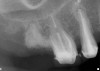

Figure 16  Radiograph showing the site after it was filled with the resorbable bone graft material and covered with the PTFE barrier.

Figure 16

Figure 17  At the time of reentry, the pure-phase β-TCP particles appeared clinically to have resorbed, preserved the full ridge width, and been replaced by bone.

Figure 17